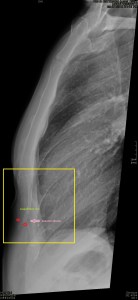

Con la eco pasa igual…cuando queremos estudiar, por ejemplo, el recto anterior del muslo en axial,perfecto…pero en longitudinal, como la imagen 2, se complica porque desde la rótula a la inserción en la cadera, tenemos mucho recorrido. En este caso hacemos lo mismo que cuando hacemos la foto del atardecer…nos ponemos en un extremo, activamos la funciona, recorremos suave y continuamente por la anatomía que queremos fotografiar y ya está…mira la pantalla y no el movimiento de tu mano,como si hicieses la foto, ves la pantalla,pero no como mueves el teléfono.

Es muy útil para lesiones que han crecido mucho y no podemos conjugar en una sola imagen, por ejemplo, un lipoma, cuando superan la medida de la huella de la sonda no son medibles, hay que usar «panoramic view», y como este caso, otros muchos.

En la imagen 3 ves una imagen de un lipoma, mide 7 cms, la huella de la sonda mide 5cms, la «panoramic view» posee una regla centimetrada que sigue el contorno de la imagen, justo en la profundidad de la misma y lo marca la flecha amarilla. La profundidad la marca la flecha roja y la flecha blanca marca el rango centimetral de los 5cms, fíjate que la línea blanca es ligeramente mayor cada 5 cms. Sirve de referencia, como en la imagen 4 donde ves una colección en el glúteo de más de 10 cms.

Técnicamente es lo mismo, ambos dispositivos hacen una suma de imágenes que se plasman en un resultado final estupendo. Toda la escena más pequeña, pero más alargada que te da percepción de toda la magnitud de aquello que pretendes estudiar, te quita algo de detalle, pero te sirve para medir perfectamente y además puedes incrementar y mover la imagen con tu track ball…

Podemos medir valores superiores a los 15cms con alta calidad de imagen…podemos llegar a medir valores por encima de los 25 cms…es verdad que no todos los equipos tienen este ajuste ecográfico, es decir, es una aplicación y por tanto hay que pagarla.